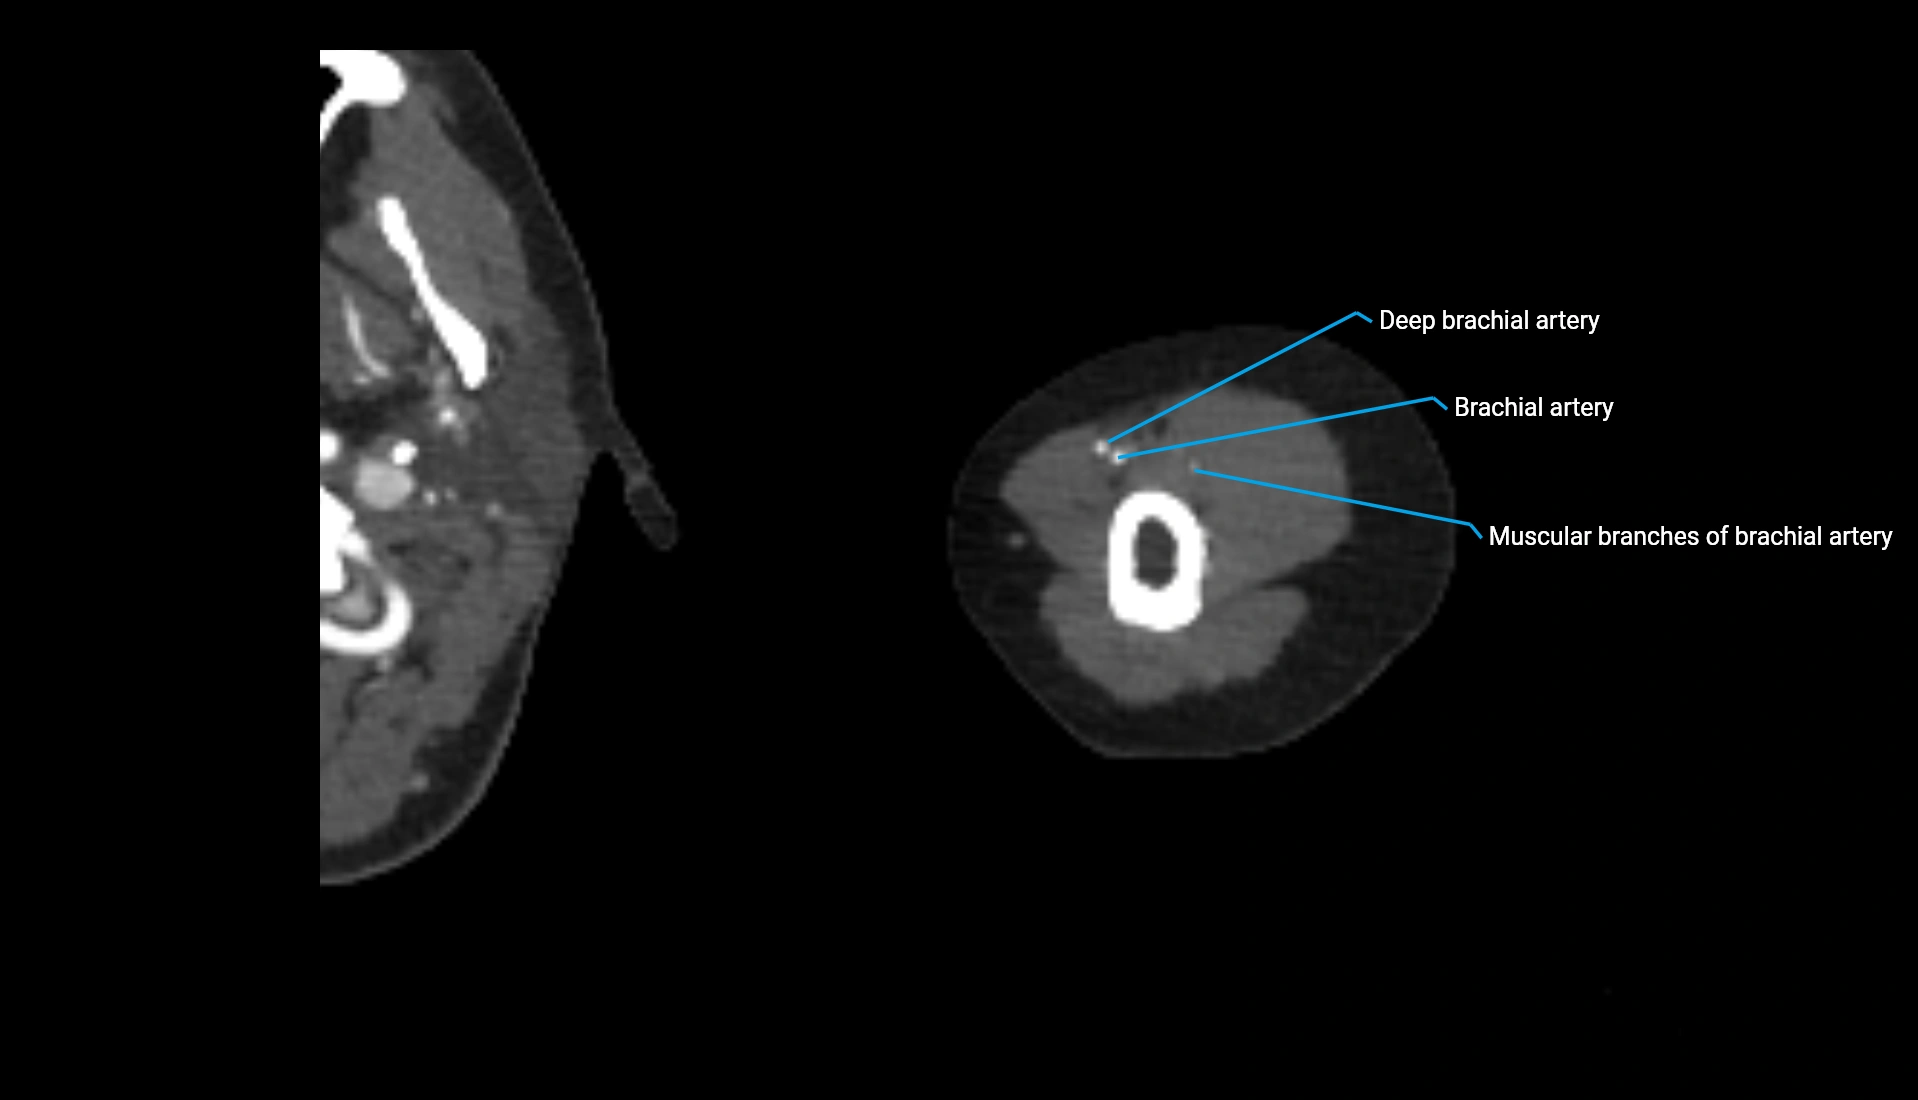

CT Appearance

Non-Contrast CT:

• Cortex: High-density, sharply defined

• Subchondral bone: Dense cancellous matrix

• Articular surface: Smooth concave contour articulating with the capitellum

• Excellent for evaluating bone integrity, alignment, and subtle fractures